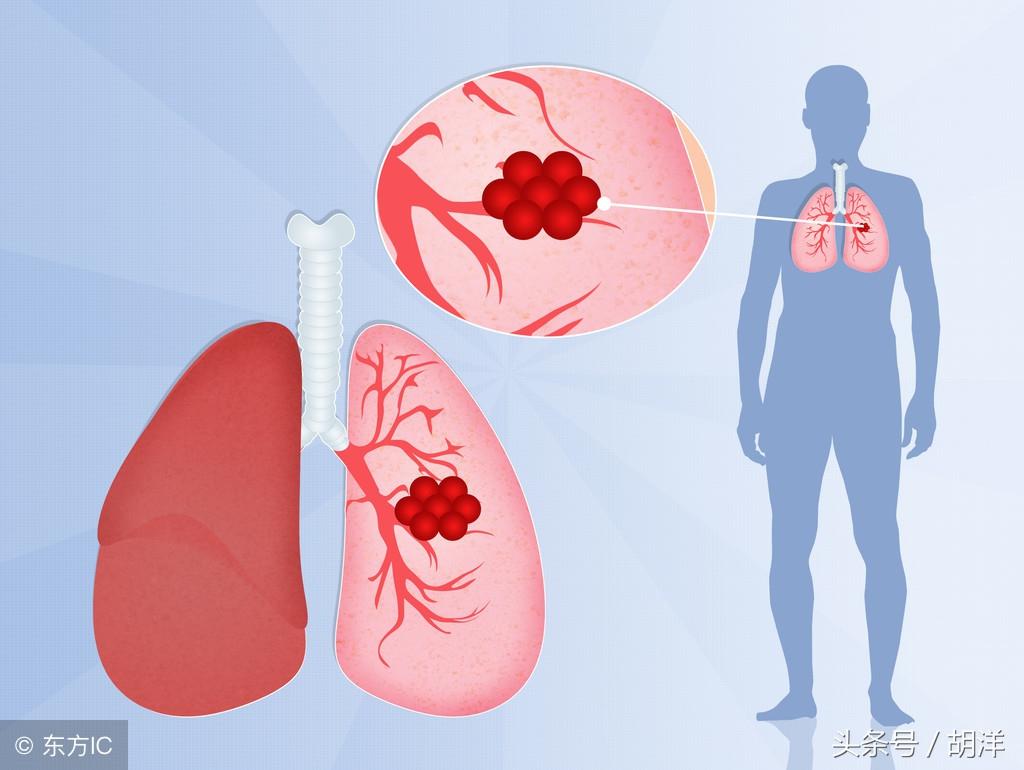

肺癌

肺癌也是较为常见的导致咯血的原因,恶性肿瘤细胞对于肺组织的侵蚀是其他疾病无法比拟的,几乎可以侵犯肺部正常组织中的所有结构,包括血管,另外,肺癌癌肿由于生长过快,其表面的细胞可能会因为得不到充足的血液供应而坏死,这样的坏死很容易产生渗血,是引起痰中带血的常见原因。